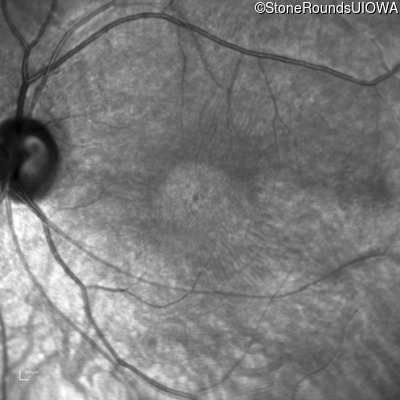

Infrared Fundus Photograph - Right - 20/100 -1 sc

Exemplar

Infrared Fundus Photograph - Left - 20/100 -2 sc